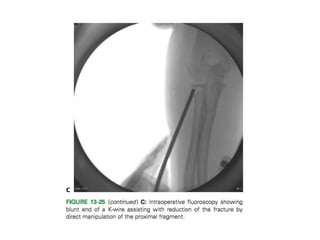

Instrument-Assisted Closed Reduction

Oblique pin insertion

Leverage techniqueLeverage technique of instrument-

assisted closed reduction of the

proximal radius

(A). Intraoperative AP

fluoroscopy image demonstrating

angulated radial neck fracture

(B). K-wire inserted at fracture

site and levering proximal

fragment into a reduced position

(C). Same wire driven through the

opposite cortex to hold reduced

position of the proximal fragment

(D).AP view of elbow following

pin removal in clinic showing

anatomic alignment of proximal

Wallace technique